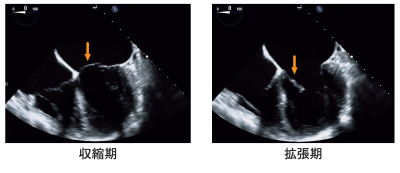

経食道心エコー図を別に示す。

矢印の構造物として正しいのはどれか。

矢印は、左心房と左心室の間の弁を示しています。